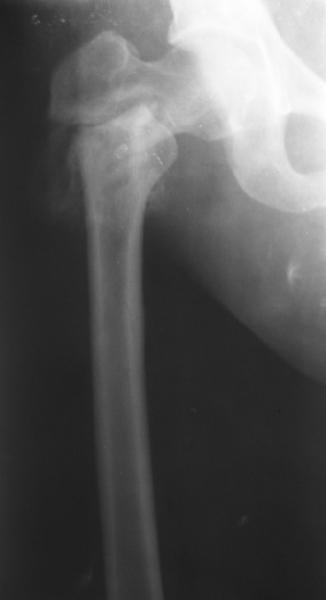

Уважаемые коллеги, хотелось бы услышать ваше мнение по следующему случаю: Относительно молодая женщина(39 лет), поступила в клинику в марте 2005 года, через 3 месяца после травмы с Неправильно срастающимся поперечным межвертельным переломом правого бедра. Был выполнен закрытый интрамедуллярный остеосинтез правого бедра канальным реконструкционным стержнем ChM. Ожидали бОльших проблем на операции, результату обрадовались. Как оказалось, зря. Сращение наступило через 3,5 месяца после операции. В ноябре 2005 года произошел перелом шейки бедра и винтов в ней. В апреле 2006 импланты были удалены. В приложении фото и рентгенограммы больной. Сопутствует ожирение 4 ст. (при росте 168 см., вес больной 140кг.), сахарный диабет II тип. Имеется медиальная неустойчивость коленного и голеностопного суставов, при нагрузке колено вальгируется на 15-20 градусов. Вопросы: 1.Целесообразность эндопротезирования (в настоящий момент передвигается на ходунках)? 2.Если ответ на первый вопрос-да, то каким протезом? 3. С какими проблемами можем столкнуться во время и после операции? Заранее благодарен за ответы. Салават Салаватов, Екатеринбург